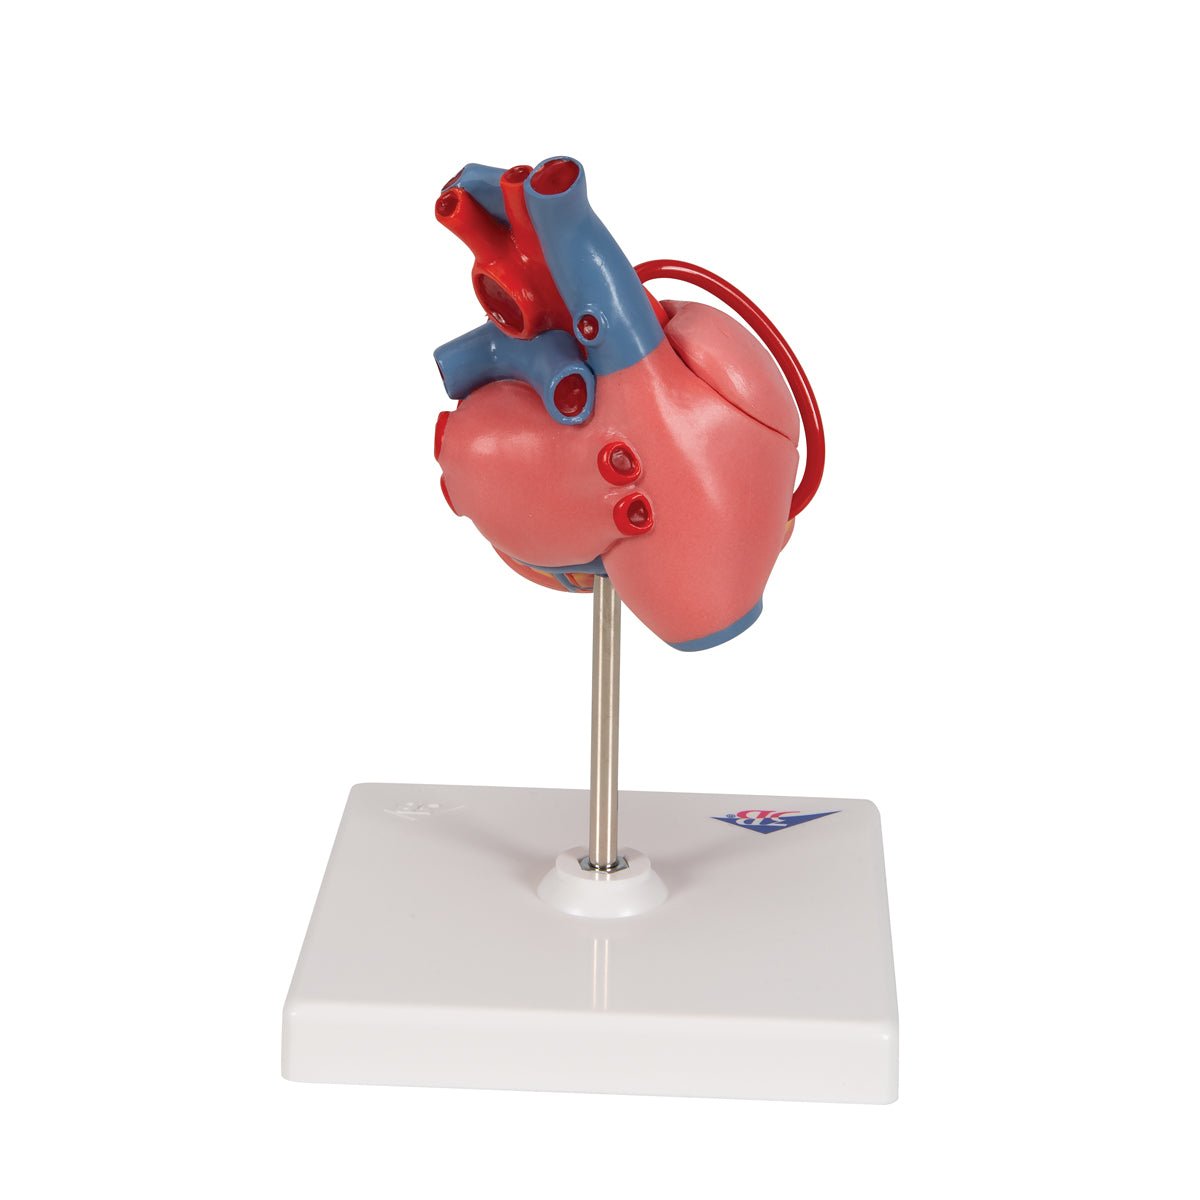

Selling anatomical models is the mainstay of eAnatomi, although we also spend a lot of resources developing our own anatomical materials such as posters. Anatomical models are used for various purposes and can show both defined tissues, organs and organ systems. Are you looking for a simple model of bone tissue or perhaps an advanced torso model based on MRI technology, you can find it all at eanatomi.com.